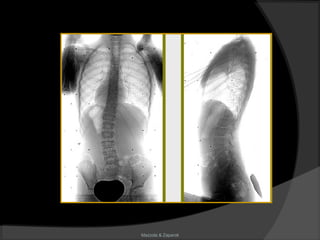

Escoliose

Mazzola & Zaparoli

Definição

“É uma deformidade ântero-posterior em

lordose, causada por um movimento em

torção de todo segmento raquidiano. Essa

deformidade se expressa lateralmente e

trata-se de uma curva reversa.”

(Perdriolle)

Aspectos radiológicos

 Topografia;

 Ângulo de Cobb;

 Rotação:

Nash-Moe

Perdriolle

 Bending – test;